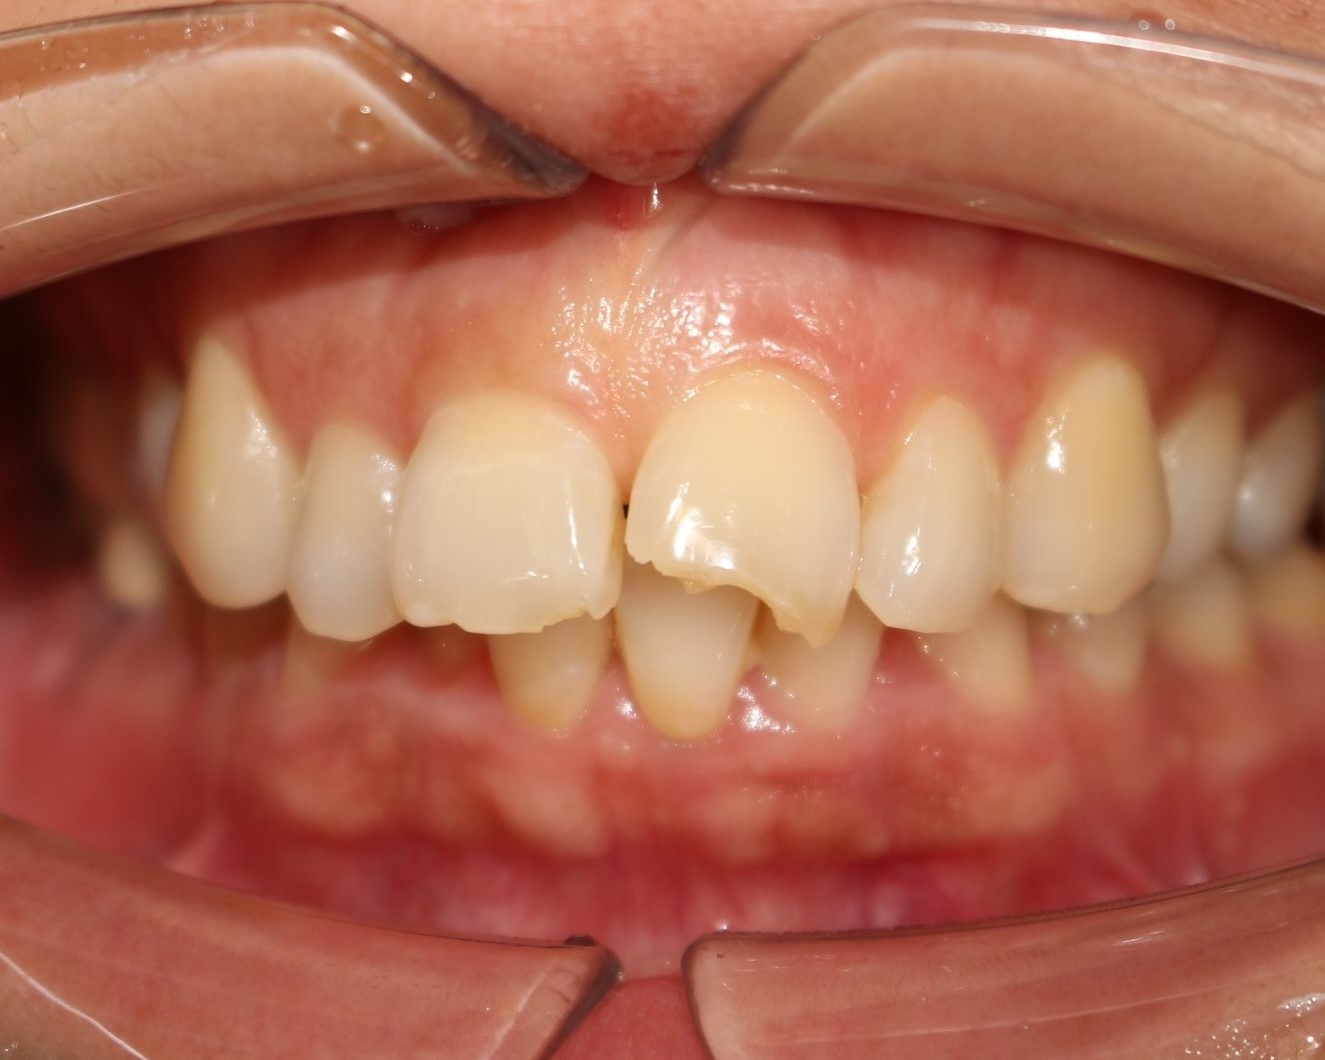

수술 전

수술 후

전치부 치아파절 크라운 치료(PFZ)

전후사진